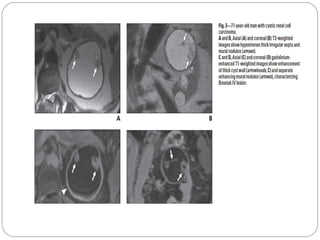

MULTILOCULAR CYSTIC RCC

20-76 years of age

Low grade tumor

Characterized by septate variably sized cysts separated from

the kidney by a fibrous capsule.The cyst fluid may be serous

or hemorrhagic and thus can be of water attenuation or

higher.

Asymmetric septal thickening may be seen

May show septal or wall calcification

Cystic clear cell carcinoma is distinguished from multilocular

cystic RCC by the presence of fewer loculations,thicker and

more nodular septa, and expansile

enhancing mural nodules.